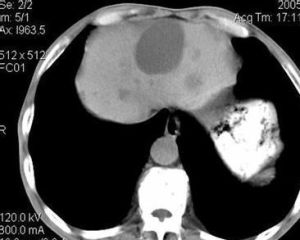

B超、CT、MR、ECT。

患者通常在40-50歲後才出現臨床症狀,與囊腫大小有關,主要為消化道症狀如消化不良、食慾減退、暖氣、噁心、嘔吐和右上腹痛,但程度不重。繼發感染後可出現寒戰和發熱。少見有巨大囊腫壓迫膽總管或肝管出現黃疸的情況。肝囊腫者檢查肝功能時多為正常。B超檢查肝區可見多個液性暗區。CT、核素掃描檢查有助於與實質性腫瘤及血管瘤相鑑別。